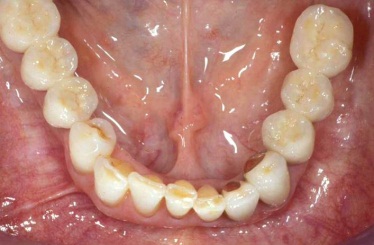

V případě chybění většího počtu zubů v postranních úsecích čelistí je možné ošetření pomocí implantátů, které nahradí ošetření pomocí snímacích náhrad kotvených na zbývajících zubech nebo patře.

Podmínkou je opět dostatečné množství kosti.

Protetické řešení může být pomocí můstku, který je kotvený na implantátech nebo pomocí jednotlivých korunek na implantátech.

V zásadě je možné do těchto můstků zařadit i přirozené zuby, zejména pokud je potřeba tyto zuby ošetřit proteticky – korunkami. Korunky nebo můstky mohou být na implantáty nacementovány nebo přišroubovány.

Zdravé zuby zůstanou zachovány a přitom náhrady jsou pevné, jako na vlastních zubech